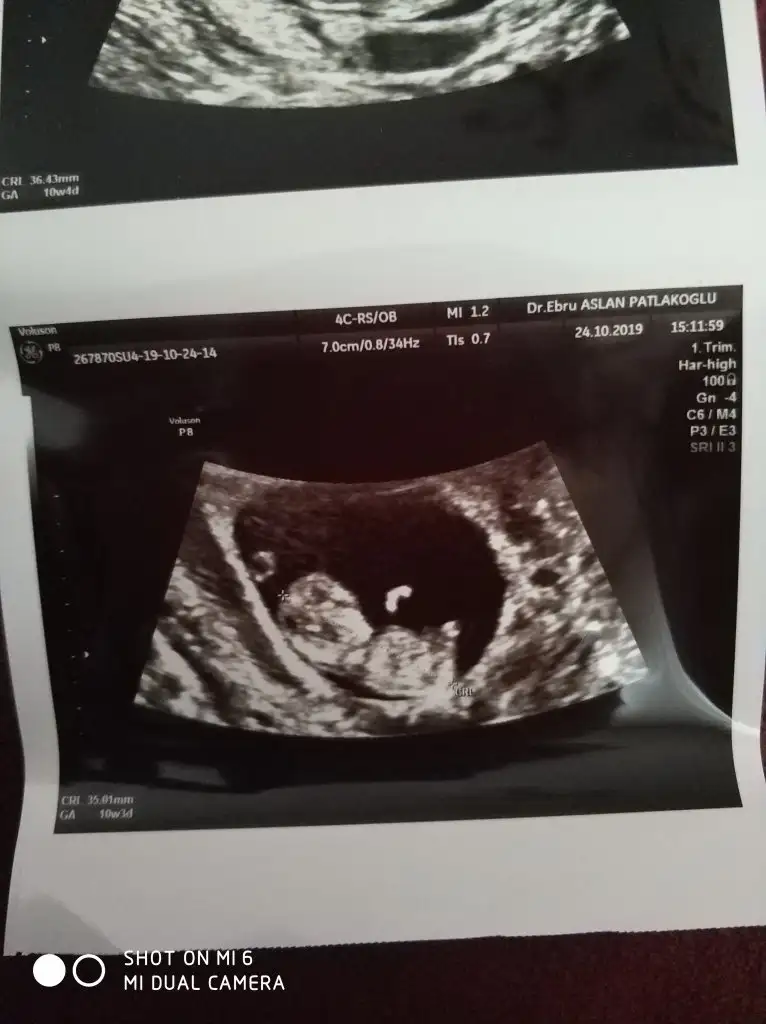

Kız gibiMerhaba hanımlar, şimdi dr.dan geldim adete göre 10+6 ultrasona göre 11+6, banada cinsiyet tahmini yapar mısınız rica etsem?

Eki Görüntüle 2550333 Eki Görüntüle 2550334